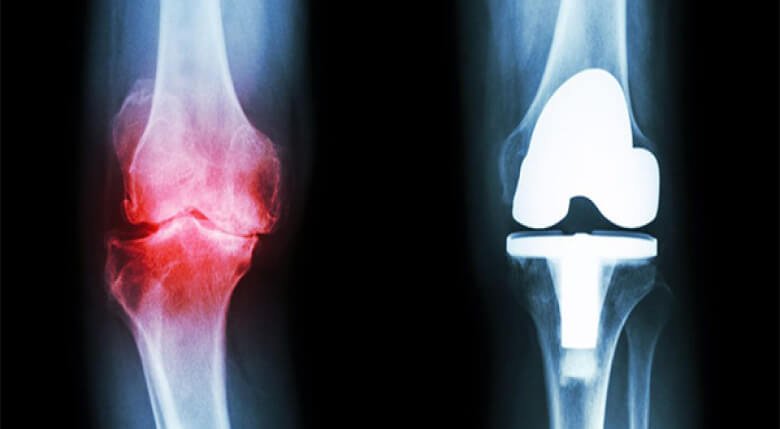

वास्तव में यह सीक्रेट तो बहुत ही सरल है। हमें दर्द की जड़ को समझने की जरूरत होती है। आज मेडिकल एनसाइक्लोपीडिया में ऑस्टियोकांड्रोसिस और ऑस्टियोआर्थराइटिस के करीब 147 कारण दिए गए हैं, लेकिन वास्तव में इन सब का परिणाम एक ही होता है। जोड़,रीढ़ की हड्डी और गद्दी की लचक चली जाना, जिससे दर्द होता है। आपको पता है यह क्यों होता है? इसलिए क्योंकि रक्त का प्रवाह ठीक से नहीं होने के कारण ये घिस जाते हैं।

नहीं। ACTIVE JOINT PAIN OIL से कोशिका के स्तर पर असर होता है और रक्त प्रभाव वापस ठीक हो जाता है। इससे जोड़ों और रीढ़ की हड्डियों की सभी प्रकार की बीमारियाँ ठीक हो जाती हैं जैसे: ऑस्टियोआर्थ्रोसिस और आर्थराइटिस, साइटिका, गठिया, रेडिकुलाइटिस, वर्टेब्रल हर्निया, चोट, फ्रैक्चर आदि। इन सभी मामलों में ACTIVE JOINT PAIN OIL का बहुत ही अच्छा असर होता है।